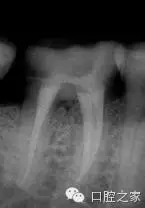

若干雜志均報道了近中牙根內(nèi)第三根管的存在。本篇系統(tǒng)性文獻回顧報道的是2.6%的第三根管發(fā)生率(圖2和3)。為了進一步定位第三根管,需要對開髓洞形進行改良。簡單地講,一旦定位了主根管,并對其進行根管預備后,使用小球鉆或超聲工作尖去除根管口間的牙本質(zhì)橋,為近中根的近中壁與髓腔形成的角提供了直視的視野,將兩個主根管間發(fā)育溝直接暴露出來。然后使用根管口探針探查根管,小號的根管銼順利的通暢根管。除此之外,手術(shù)顯微鏡的運用進一步提高了發(fā)現(xiàn)和治療副根管的可能性。還有一點必須要考慮的是近中根的遠中凹度,為了避免出現(xiàn)帶狀穿孔,第三個近中根管的預備過程要使用小號的根管銼謹慎小心的預備。中間近中根中根管完全獨立的患牙占整個病例中的25%。